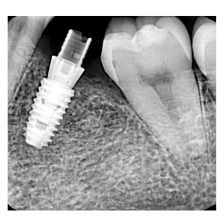

―症例集―

症例一覧